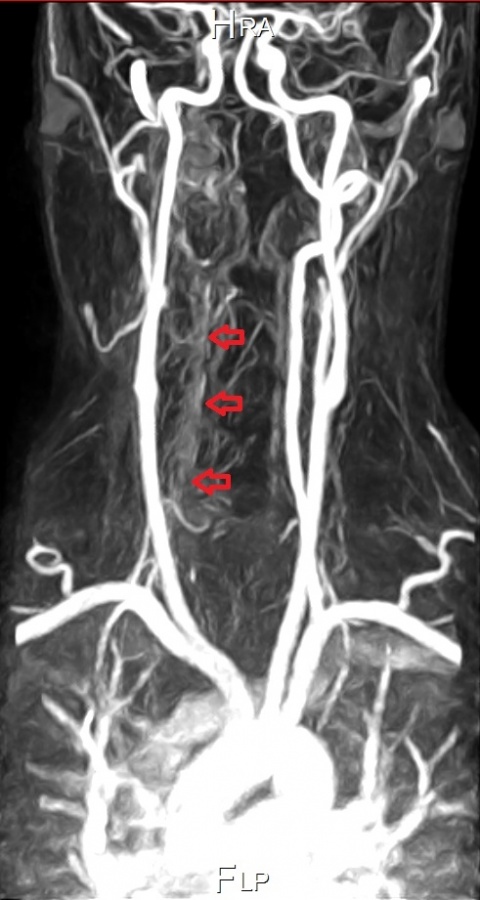

Die A. vertrebralis stellt sich links kontinuierlich und

kräftig dar. Rechtsseitig kommt es im kompletten

Verlauf der A. vertebralis durch die Dissektion und

den damit verbundenen verminderten Fluss zu einer

deutliche Signalabschwächung (rote Markierungen).

Im MRT vom Folgetag wurde ein langstreckiges Wandhämatom der rechten Arteria vertebralis, im Sinne einer entsprechenden Dissektion, nachgewiesen.